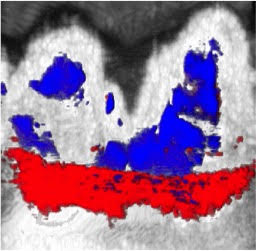

Noua tehnică folosește cerneala de sepie ca substanță de contrast. Pacientul își clătește gura cu o soluție din cerneală de sepie, apă și amidon de porumb, iar nanoparticulele de melanină din cerneală rămân în șanțul gingival. Acestea absorb lumina, iar când medicul proiectează o lumină laser pe dantură cerneala se încălzește și se umflă, creând în șanțul gingival diferențe de presiune ce pot fi cu ușurință detectate cu ultrasunete. Astfel se realizează o „hartă” a adâncimii șanțului gingival din jurul fiecărui dinte.

Substanța neagră colorează spațiul dintre gingie și dinte, însă este îndepărtată cu ușurință în urma unui periaj dentar simplu, cu pastă de dinți.

Metoda de imagistică fotoacustică a fost testată pe modele animale și s-a dovedit a fi în mod constant mai exactă în multiple teste, față de sonda parodontală. În viitorul apropiat, cercetătorii urmează să testeze metoda pe oameni, să îmbunătățească gustul soluției (care acum este sărat-amărui) și să simplifice aparatura laser.